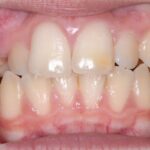

Initial

Final